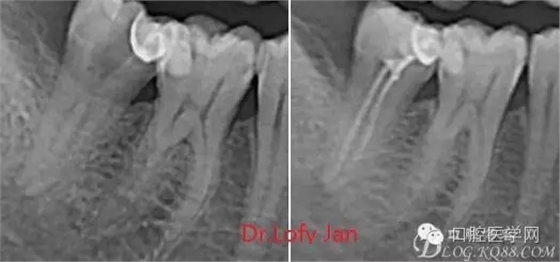

曲面斷層片在未試尖根管治療中的病例整理

前言:自己做的一些曲面斷層片在未試尖根管治療中的病例整理,發(fā)現(xiàn)問題很多包括自身的,技術(shù)的,還有設備的問題,予以總結(jié)整理并期待進一步提高。

《數(shù)字化根尖片、曲面斷層片、CBCT測量牙齒長度準確性的比較研究》文中顯示:平行投照數(shù)字化根尖片影像長度和牙齒實際長度之間無顯著性差異(P0.05);數(shù)字化曲面斷層片影像長度和牙齒實際長度之間有顯著性差異(P0.05),平均失真率為17.05%。CBCT冠狀面測量結(jié)果中除上頜前磨牙區(qū)、下頜前磨牙區(qū)與真實長度差異無統(tǒng)計學意義(P0.05)外,其余6個分區(qū)差異均有統(tǒng)計學意義(P0.05);矢狀面測量結(jié)果中上頜磨牙區(qū)、下頜磨牙區(qū)、下頜前磨牙區(qū)、下頜尖牙區(qū)、下頜前牙區(qū)與真實長度比較差異均有統(tǒng)計學意義(P0.05)。結(jié)論平行投照數(shù)字化根尖片較曲面斷層片和CBCT能更加精確地反映牙齒的真實長度。

病例分析:曲面斷層片在x線輔助診斷與檢查中目前大多數(shù)文獻和著作都建議只能作為初診拍片檢查手段,不能作為終末疾病的確診與手術(shù)療效的評價指標,臨床大部分中小型門診都因為設備不齊全導致信息偏差很大。